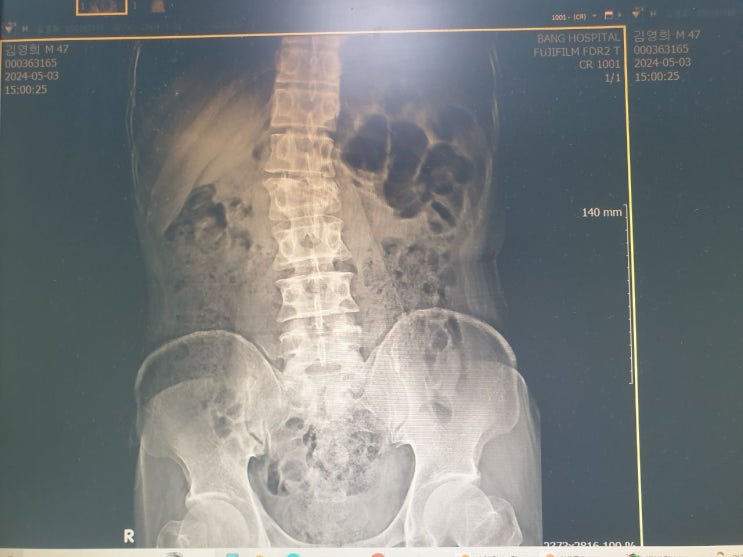

요추 압박골절 치료기록 병원 방문 63일차(금요일)

요추 압박골절 치료기록 병원 방문 63일차(금요일) 어제 병원을 방문하였습니다. 요추 압박골절 치료 중 두...

허리 척추골절 치료 두달 간의 기록. 완치 축하! 61일차 (수요일)

허리 척추골절 치료 두달 간의 기록. 완치 축하! 61일차 (수요일) 진정한 의미의 완치는 아니지만 완치라고...